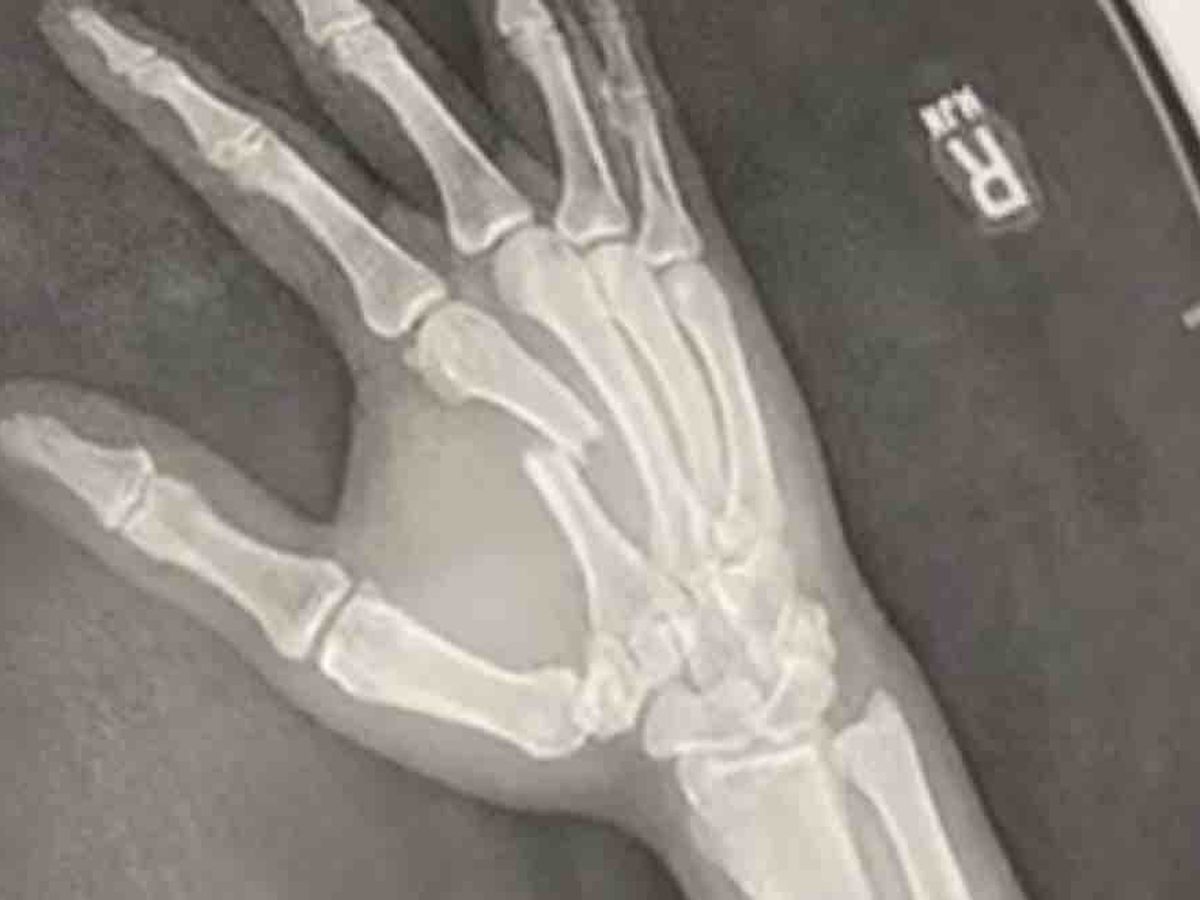

My brother Cain recently had an accident and broke his hand pretty badly. He will need surgery to fix the break and the costs are overwhelming. Any amount you can donate to help cover the cost of his surgery helps! Thank you in advance!

Cain Delos Santos